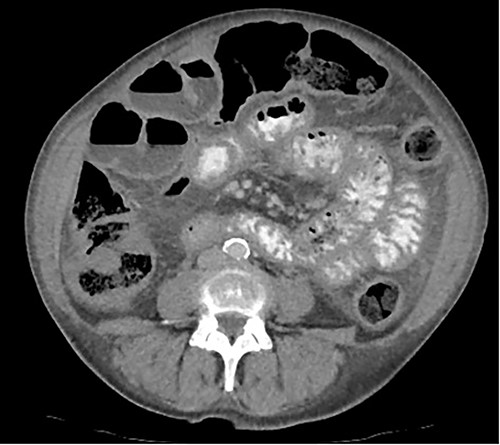

A 76-year-old lady presented to the outpatient clinic with a history of lower abdominal bloating and lethargy for 1 week. The patient denied abdominal pain, nausea, altered bowel habits or GI bleeding. Her past medical history included gastroesophageal reflux disease, ulcerative colitis and a previous hysterectomy. Physical examination exhibited pallor of the conjunctiva, distended abdomen with visible peristalsis on inspection but soft, non-tender on palpation and absence of ascites. Laboratory testing found normocytic normochromic anaemia, thrombocytosis and a positive myeloma screen with elevated kappa to lambda free light chain ratio despite normal renal and liver function. An ultrasound of the abdomen was unremarkable. Computed tomography (CT) with IV contrast of the abdomen revealed diffuse thickening of the small and large bowel with the small bowel dilated throughout. Magnetic resonance imaging of the small bowel showed multiple abnormally thickened loops of the jejunum and proximal ileum with a maximal wall thickness of 0.9 cm (Figs 1 and 2). Gastroscopy revealed severe distal oesophagitis, the stomach contained patchy telangiectasia and gastritis with sloughy mucosa at the incisura in addition to duodenitis with stricture at the second part of duodenum (D2) (Figs 3 and 4). Histopathology from the biopsies of the gastric incisura, D2 and the proximal jejunum displayed reactive changes with intramucosal haemorrhage and extensive deposition of pink amorphous, eosinophilic material on haematoxylin & eosin (H&E) stain. The deposits were predominantly seen in the proximal jejunum with a positive Congo red stain showing apple-green birefringence under polarized light (Figs 5 and 6). The patient was referred to Haematology, and a bone marrow aspirate and trephine biopsy revealed proliferation of 15% mature plasma cells consistent with the diagnosis of myeloma.

Coronal magnetic resonance image of abnormal thick-walled loops of jejunum and proximal ileum without focal stricture.